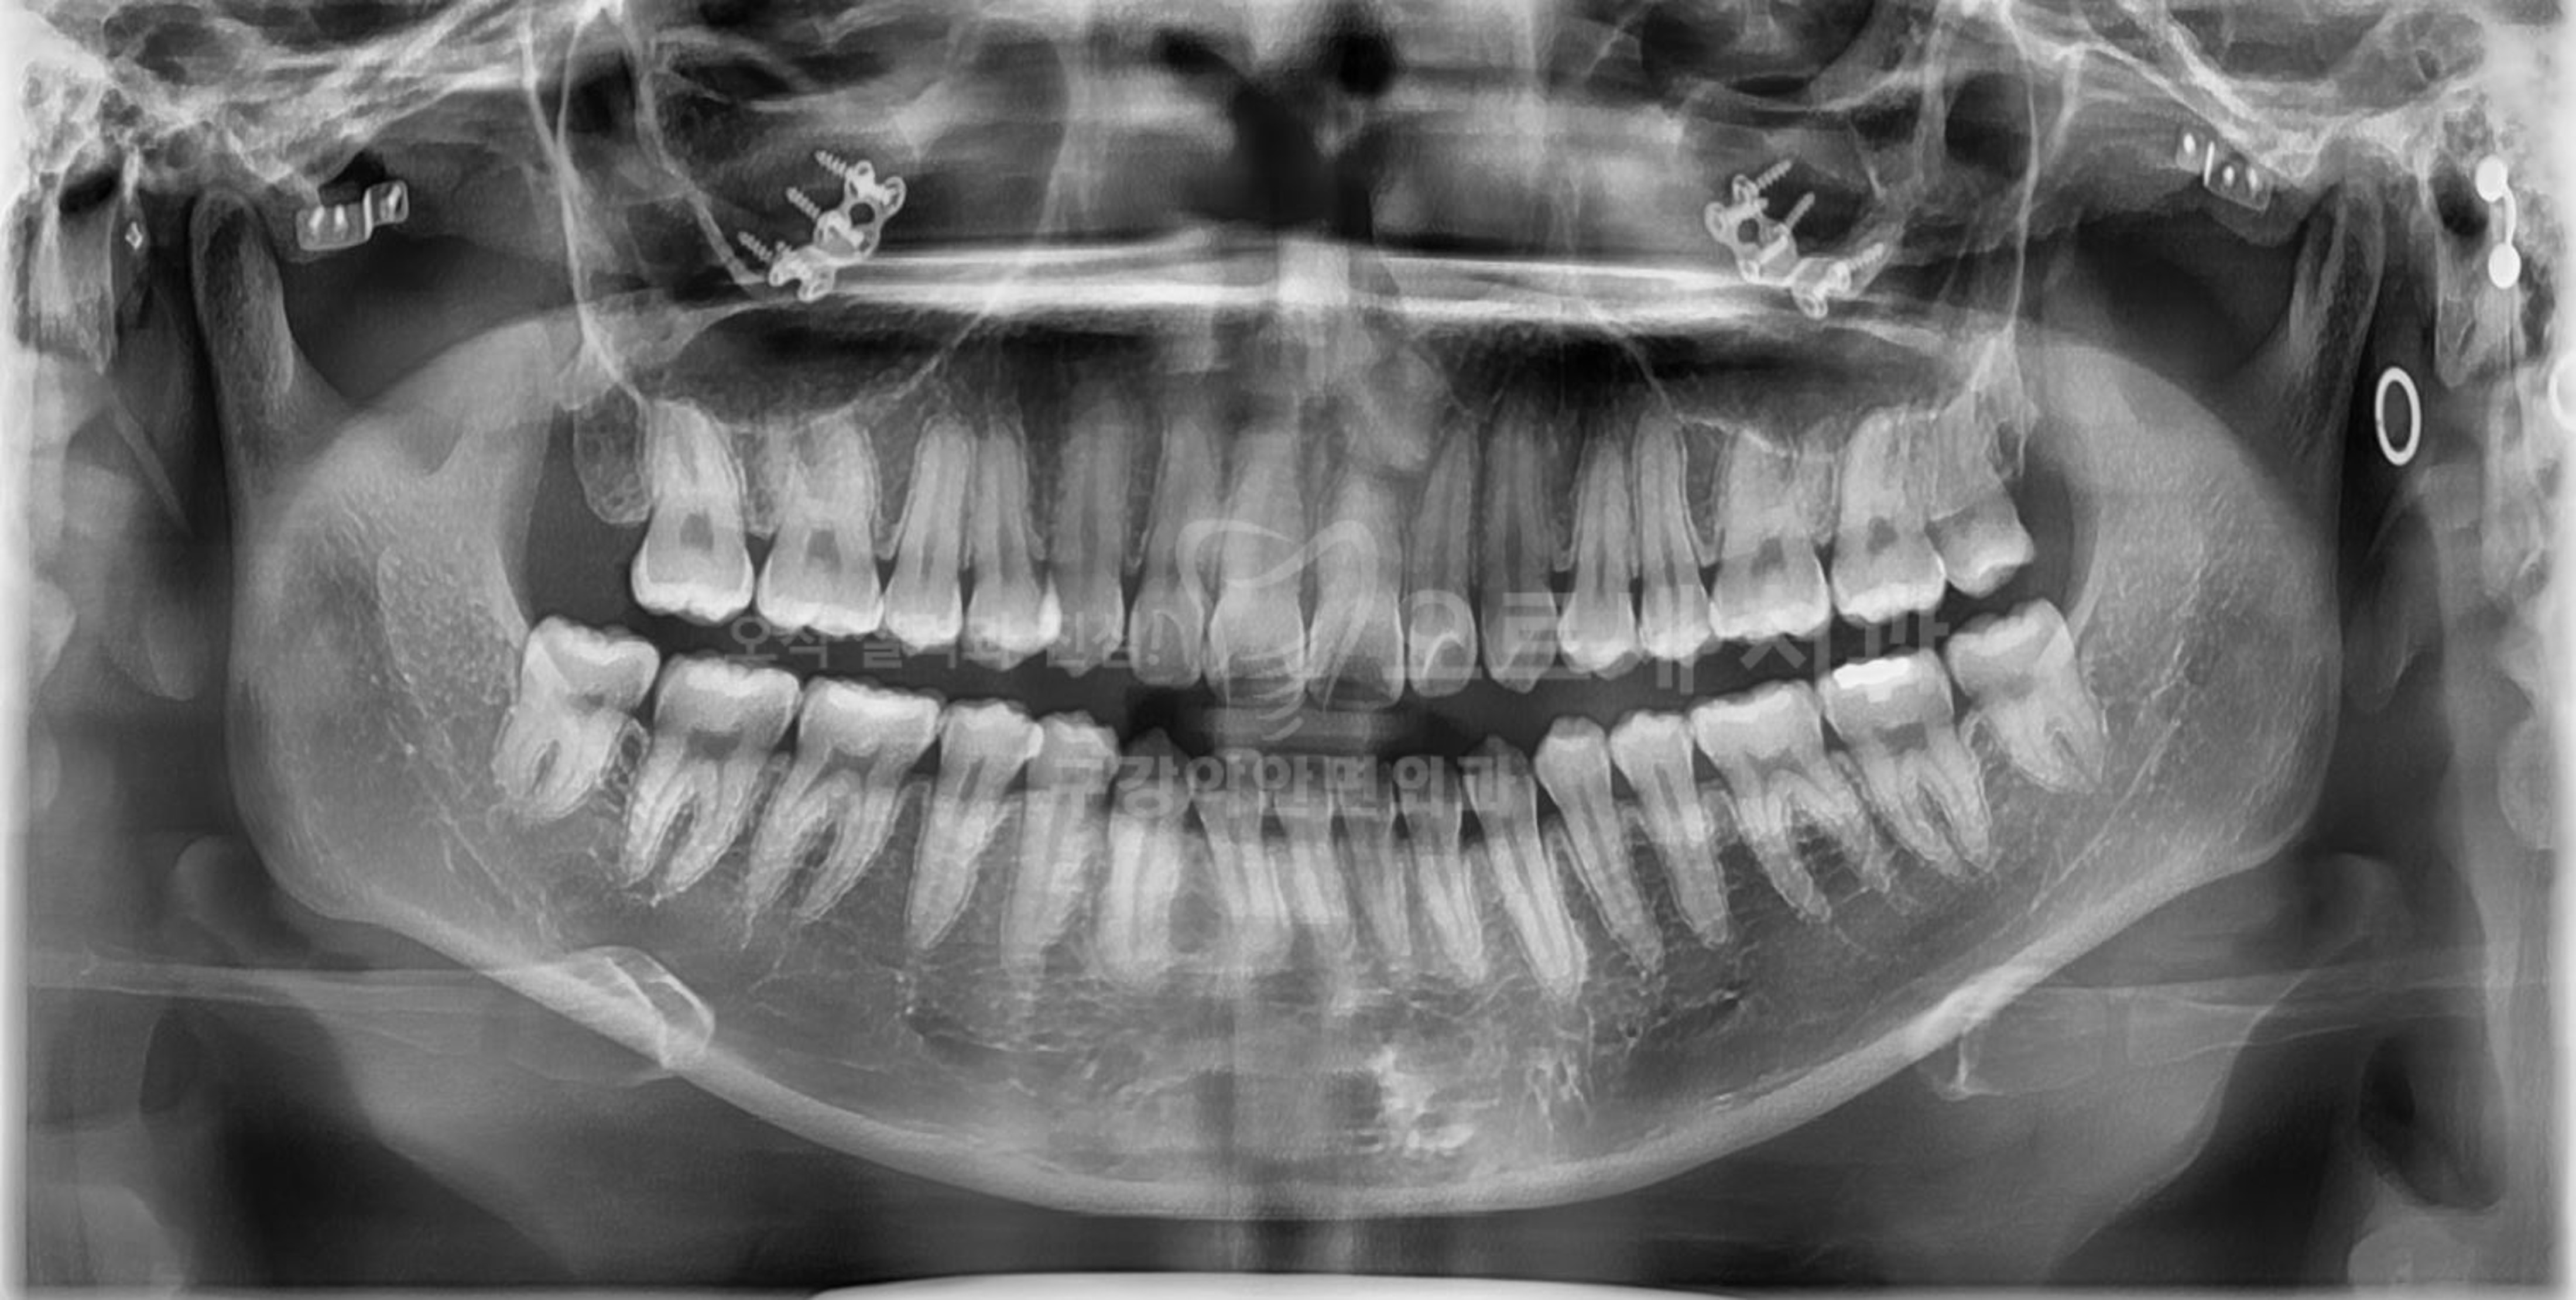

가능하다면 20대에는 발치하는 것이 좋다는 사랑니, 내게 있는 것이 알고 있어도 막상 치과를 향해 발걸음을 떼기가 쉽지 않으시죠. 잇몸 염증과 통증, 심한 경우 앞에 어금니 충치까지 퍼뜨리는 사랑니는 거의 대부분 빼야 하는 경우가 많습니다. 역삼 근처에서 쉽게 찾아올 수 있는 저희 치과에서는 국제구강악안면외과 전문의 원장님께서 직접 누운 매복 사랑니 발치를 진행하고 계신데요. 간혹 신경 손상 등의 합병증 얘기를 다니던 치과에서 듣고 차일피일 발치를 미루다 더 큰 문제를 안고 오시는 경우도 있습니다. 그래서 많은 경험 상 가능하다면 제대로 나와 있는 경우가 아니면 거의 대부분의 매복 사랑니는 빼는 것이 낫다는 의견입니다. 양쪽 아래 사랑니가 있다고 해서 하루 만에 모두 발치하는 경우는 많지 않고요.. 대부..